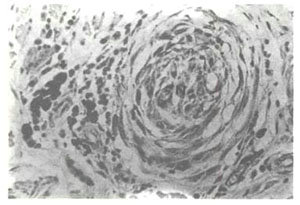

影响白癜风黑色素合成的因素之二:黑色体从黑色素细胞向临近角远细胞移行过程受阻

经我们多年观察发现:人体皮肤颜色主要因黑色素细胞的活性差异而不同,但皮肤颜色都不一定随黑色素细胞内黑色体增加而加深,而主要取决于黑色体从黑色素细胞向临近角远细胞移行的过程是否通畅。如皮肤炎症后色素脱失就是由于表皮细胞受损后,黑色体不能通过表皮细胞通畅排泄,而导致黑色体阻治于黑色素细胞内,使继发黑色素细胞功能减退。

影响白癜风黑色素合成的因素之三:黑色体的生成、降解缓慢

临床上可见到的青色色素异常如青痣、蒙古斑、太田氏痣伊腾氏痣等,均由于真皮黑色素细胞内黑色体的生成、降解进行缓慢之故。